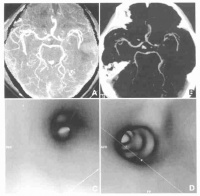

7.脑CT检查; CT诊断颅内肿瘤主要是根据肿瘤组织的密度改

颅内肿瘤

变和肿瘤对脑室系统的压迫移位来判断。有些肿瘤显示密度高,CT图像清晰;有的肿瘤因有钙化沉着,对比清楚;有些肿瘤或因瘤组织坏死,或因病灶周围水肿等变化而显示为均匀或不均匀之低密度区。颞叶肿瘤多为胶质瘤和脑膜瘤,CT检查多显示为高密度区,亦有少数肿瘤有钙化,囊变、坏死、水肿等显示其不同的密度变化。侧脑室和第三脑室常见受压、变形、移位等。